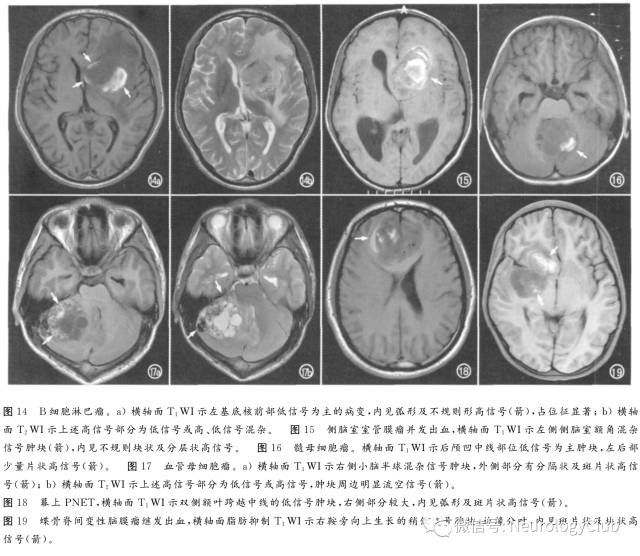

1. 原发脑肿瘤

①垂体瘤:囊变、出血、坏死常见于10mm以上者,急性出血可导致肿瘤快速增大及压迫视交叉和垂体其余部分,出现急性视力下降及内分泌功能异常,并伴头痛,称垂体卒中,溴隐亭治疗者出血发生率增加;亚急性期MRI表现为T1WI高信号,脂肪抑制无信号下降(图10),随访可见病变缩小及囊腔形成。主要应与Rathke裂囊肿及颅咽管瘤鉴别。②胶质瘤:间变性星形细胞瘤、多形性胶质母细胞瘤(图11、12)和少突胶质瘤(图13)易出血,尤其是镜下可见的出血。③其它肿瘤如淋巴瘤(图14)、室管膜瘤(图15)与室管膜下瘤、髓母细胞瘤(图16)、血管母细胞瘤(图17)、原始神经外胚层肿瘤(图18)、表皮样囊肿及神经源性肿瘤,甚至少数脑膜瘤(图19)也可继发出血,形成瘤内T1WI高信号、甚至囊液-血液平面。

2. 转移瘤

转移性肿瘤如支气管肺癌(图20)、肾细胞癌、黑色素瘤、绒癌(图21)、甲状腺癌最易出血,且常为多发性,短T1成分表示亚急性期及慢性早期出血。主要与海绵状血管瘤及其它隐匿性血管畸形相鉴别。增强扫描时非出血部分强化以及脑外肿瘤史有助于诊断。